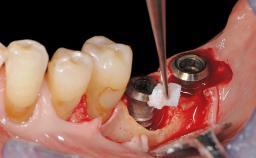

Surgical Management of Peri-Implantitis: Removal of Implant Due to Recurrent Infection Using an Implant-Retrieval Tool

Despite anti-infective surgical treatment, some patients may experience recurrent infection and progressive bone loss requiring additional treatment. This case describes a conservative approach using an implant retrieval tool without the need for excessive bone removal or use of a trephine.

A 65-year-old female patient was referred to the periodontist for assessment and management of infection associated with an implant at site 12. The general dentist had noted suppuration on probing during examination.